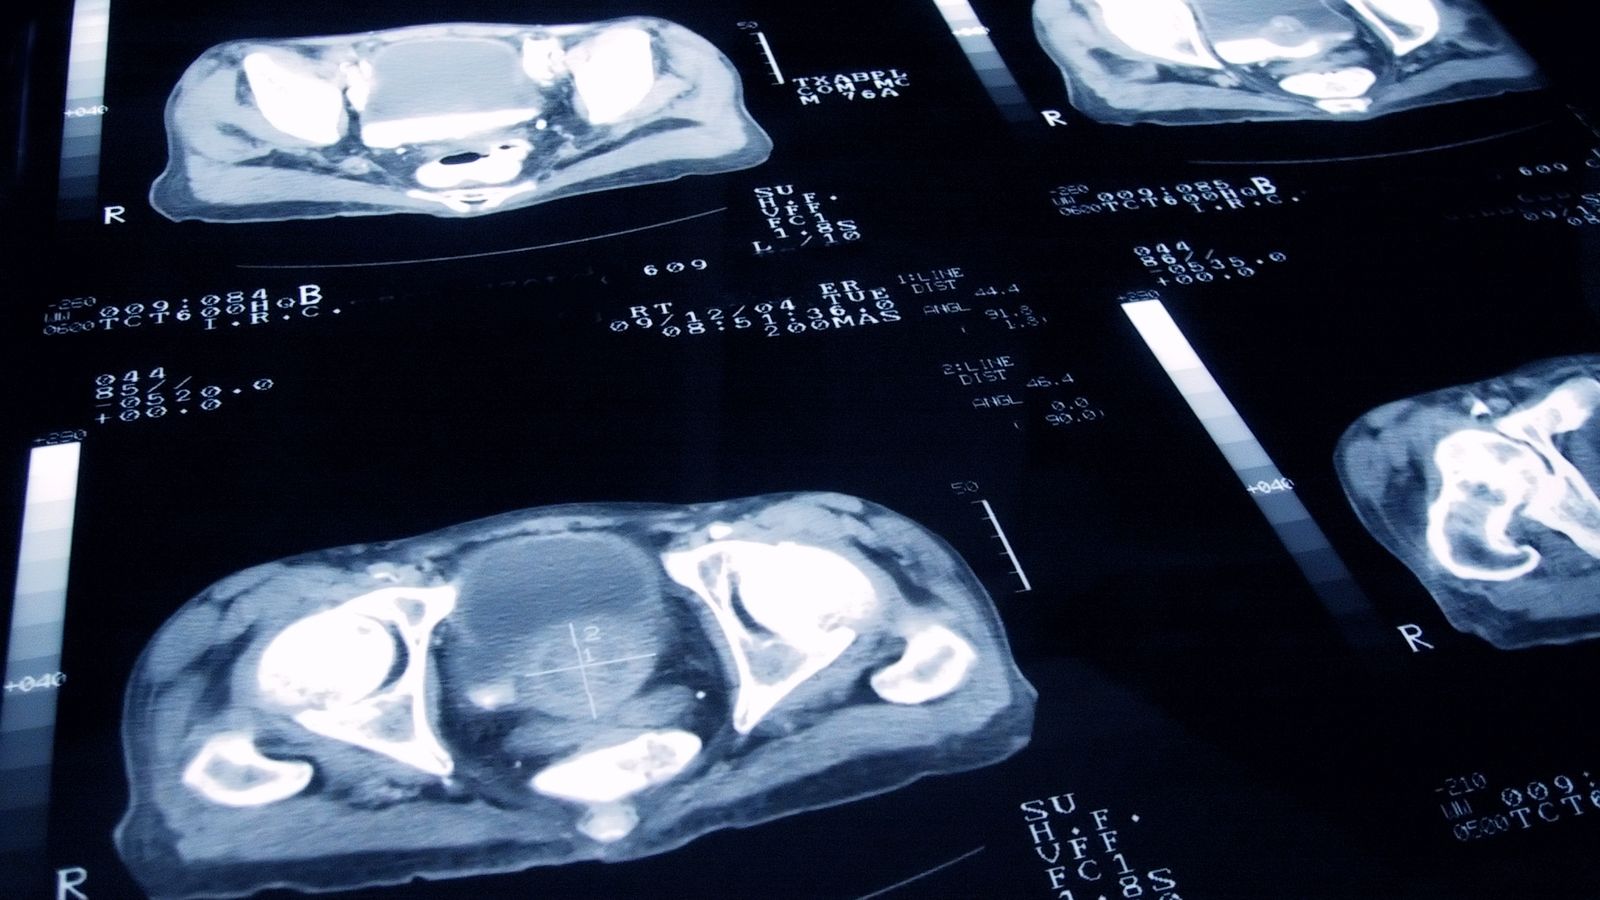

La lutte contre le cancer a connu un tournant décisif au Royaume-Uni, avec une annonce récente de Cancer Research UK qui révèle une baisse significative des taux de mortalité liés à cette maladie. Cette information, qui pourrait sembler alarmante pour certains, est en réalité un signe d’espoir et de progrès dans le domaine de la santé publique.

Les chiffres révèlent que les taux de mortalité dus au cancer au Royaume-Uni ont diminué de 11 % au cours de la dernière décennie. En effet, 247 personnes sur 100 000 sont estimées mourir du cancer chaque année, ce qui représente une baisse impressionnante de 29 % par rapport au pic de 1989, où le taux était de 355 pour 100 000.